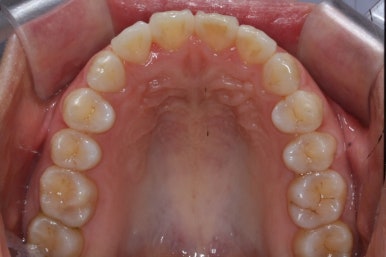

부산앞니교정 키다리아저씨치과에서 시행한 이번 MTA 부분교정의 전후 비교입니다.

위아래 앞니가 가지런해졌고, 작은 앞니의 얼룩무늬도 없어졌네요.

어쨌든, 앞니는 가지런하게 마무리가 잘 되었고, 앞니 안쪽에는 유지철사를 부착하고 치료를 종료하였습니다.